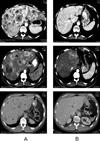

Figures